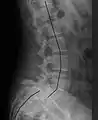

X-ray of measurement of spondylolisthesis at the lumbosacral joint, being 25% in this example

X-ray picture of a grade 1 isthmic anterolisthesis at L4-5